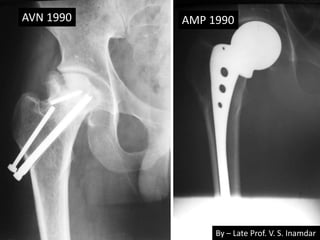

• 22 years old male had RTA – fracture neck

femur. 1986

• Operated by multiple Knowles Pins.

• Broken pins noted – 1988 – fracture united.

• AVN – 1990 – AMP done.

• Pain in anterior thigh 2002 due to broken

stem.

• Last follow up 2006.

1986 Knowles pinning

Pins breakage 1988

By – Late Prof. V. S. Inamdar

AVN 1990 AMP 1990

2002 2006